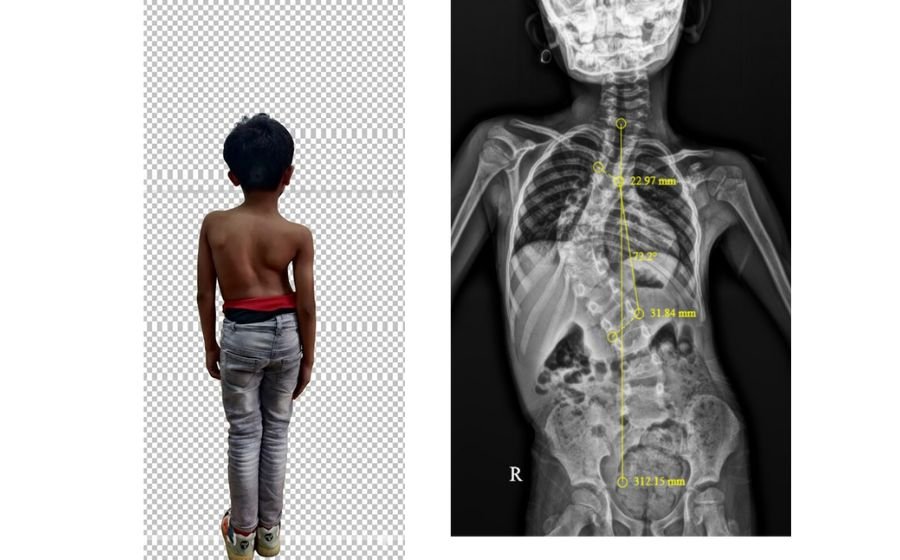

Spine Curves

Spinal deformities occur when the spine curves abnormally—sideways in scoliosis or forward in kyphosis. These changes can affect posture, balance, back pain, and sometimes breathing. Children may develop scoliosis during growth, while adults often develop deformity from degeneration, arthritis, or previous spine problems. Evaluation includes full-length X-rays and alignment analysis. Treatment depends on curve severity: smaller curves are observed, moderate curves may need bracing, and larger curves can require corrective surgery. Advanced modern techniques ensure safer correction, improved alignment, and long-term functional recovery.